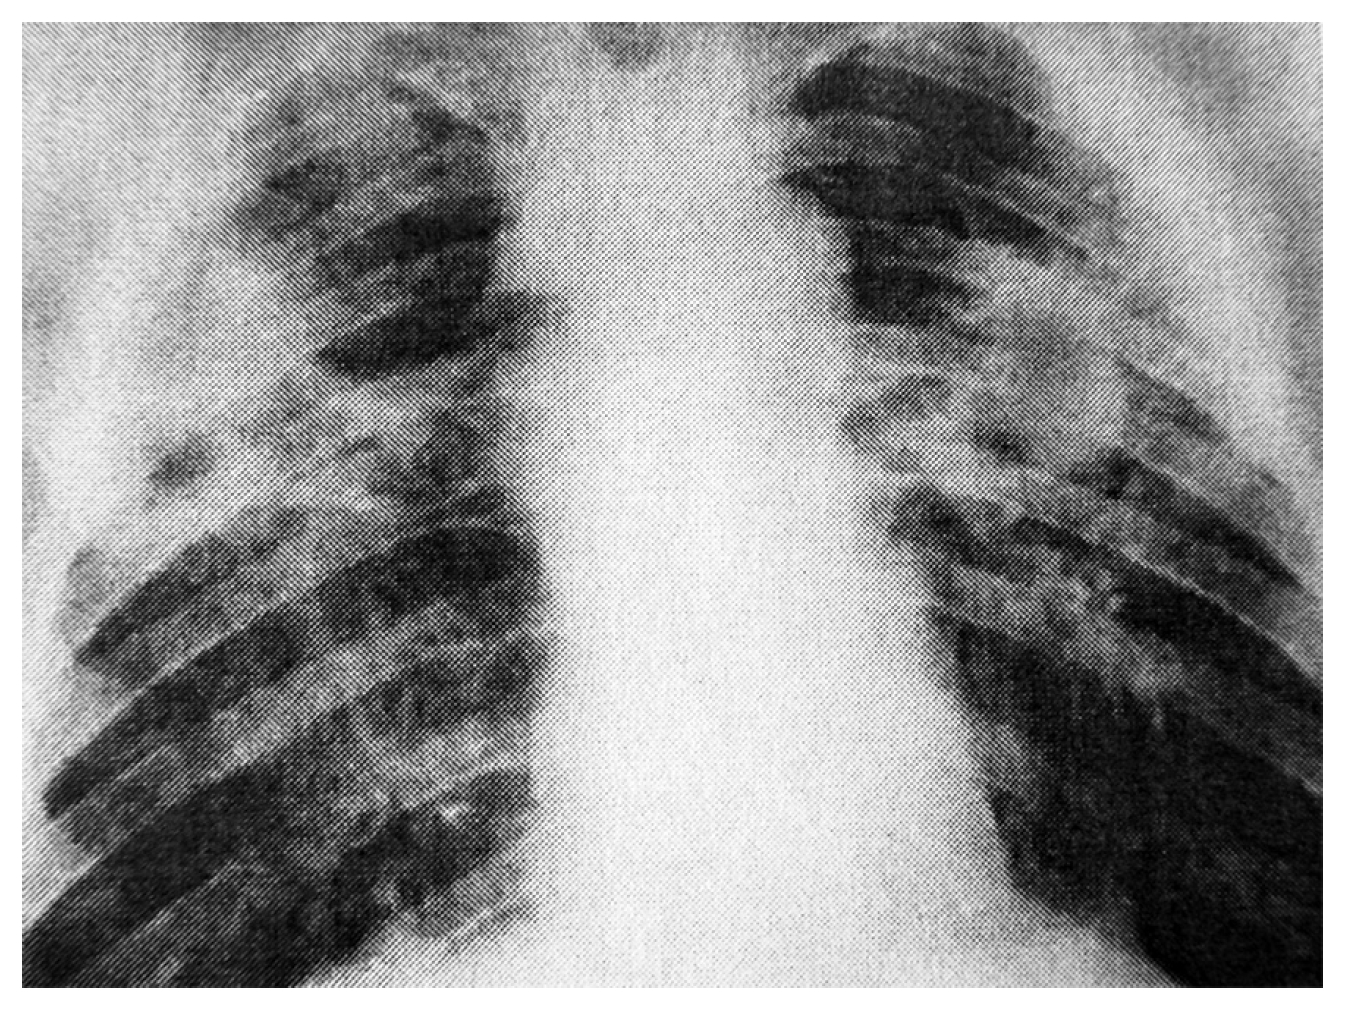

Рентгенологически выявляются интерстициальный ветвисто-сетчатый фиброз (2s) и мелкие (2р) узелковоподобные тени, расположенные преимущественно в средних и нижних отделах и на периферии. В латеральных отделах имеются узелки с тенденцией к слиянию в более крупные (q). Обнаружены рассеянные обызвествленные очаги в нижних отделах в диаметре 0,3–0,5 см больше справа. Корни уплотнены, расширены. Определяется повышенная прозрачность легочных полей в верхних долях (рис. 1).

Рис. 1. Рентгенограмма грудной клетки больного К.